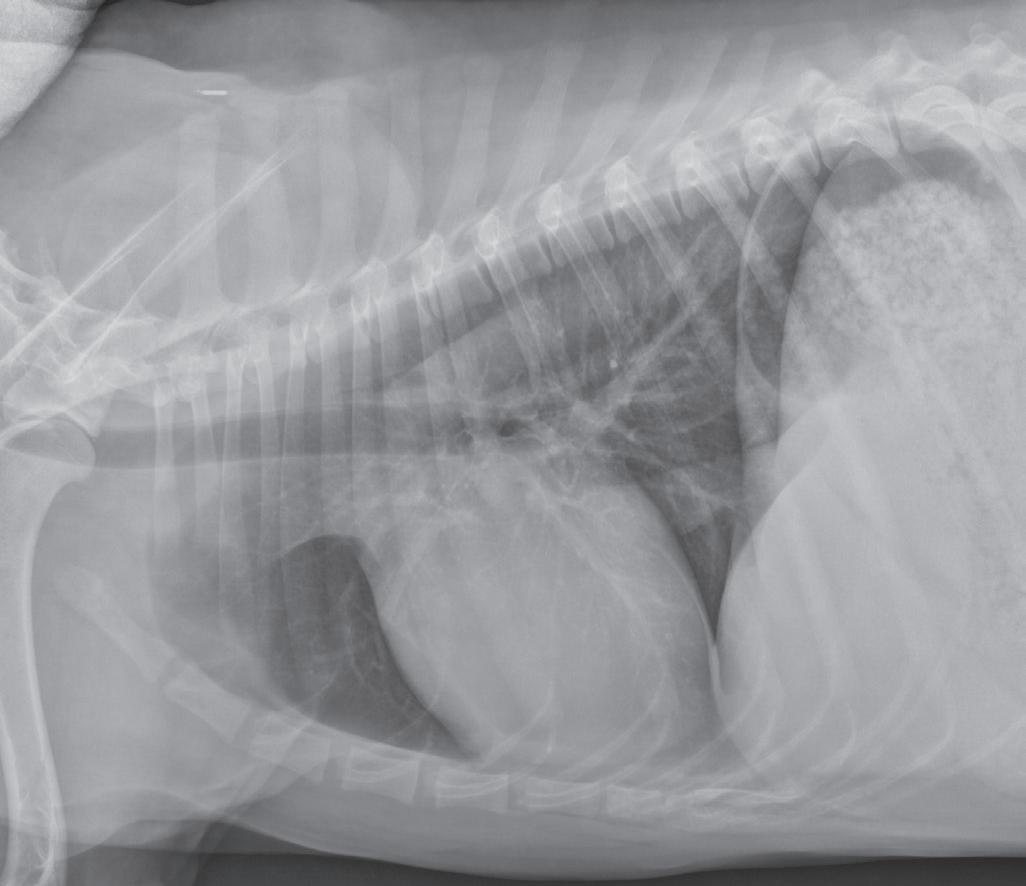

n Lateral images of any body part should be oriented with the cranial or rostral aspect of the body heading to the examiner’s left (Figure 1-2).

Correct orientation of a lateral view of any body part. A lateral view of the thorax is shown here.

Figure 1-2.